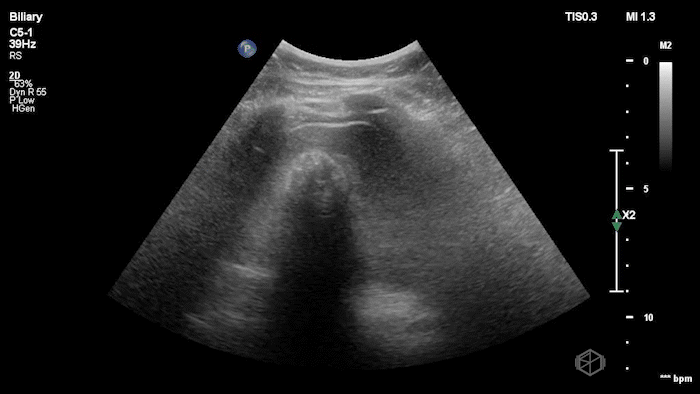

Dr. Flouskakos is on the US rotation currently and was scanning a late 80’s female with mild left lower quadrant and left flank pain when he noticed the following findings:

Upon scanning the aorta, it was noted that the patient an enlarged infra-renal abdominal aorta with an eccentric left thrombus, measuring approximately 4.05cm consistent with an abdominal aortic aneurysm. On lateral view the aneurysm appears more saccular than fusiform. CT was done which confirmed the finding: Saccular infrarenal abdominal aortic aneurysm with partially thrombosed aneurysm sac eccentric to the left measuring up to 4.0 cm.

Diagnosis: Saccular aortic aneurysm